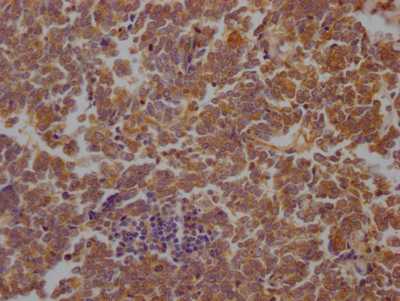

DescriptionSTAT3 Recombinant Monoclonal Antibody [3A9]. Unconjugated. Raised in: HEK293F Cell.

ApplicationELISA, WB, IHC; Recommended dilution: WB:1:500-1:5000, IHC:1:50-1:200